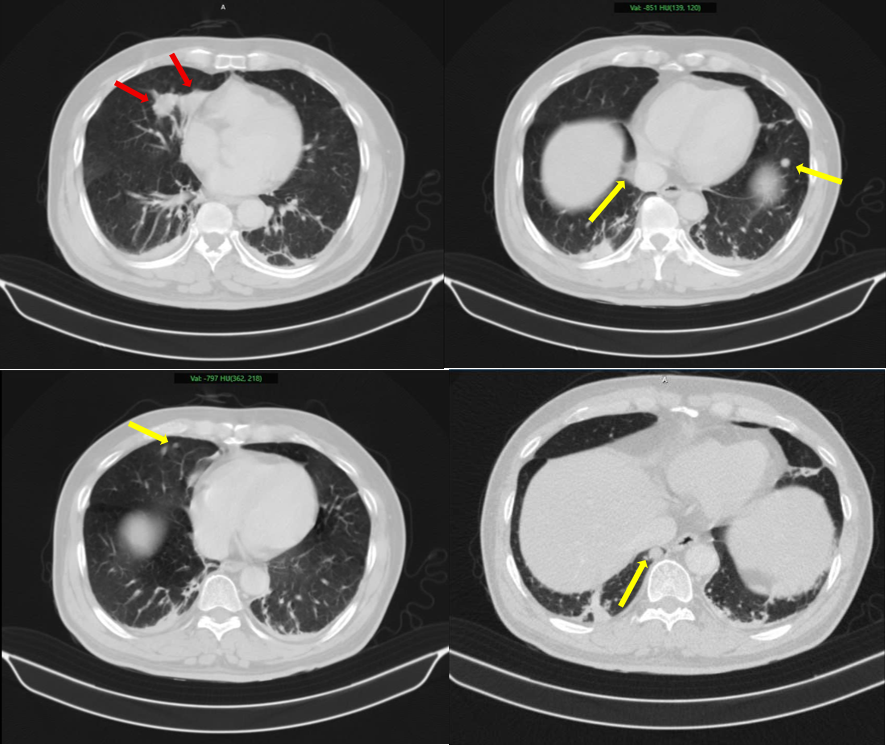

PNO - Người đàn ông phát hiện mắc cùng lúc hai loại ung thư nhưng có nguồn gốc hoàn toàn khác nhau, không phải di căn chéo.